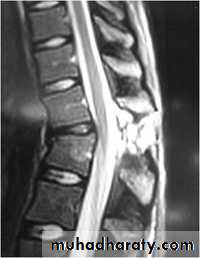

MRI :

Accurate assessment of soft tissue.1 - Neurological or cord injury .2 - Ligament injury.3 - Disc herniation.

4 - Hematoma.